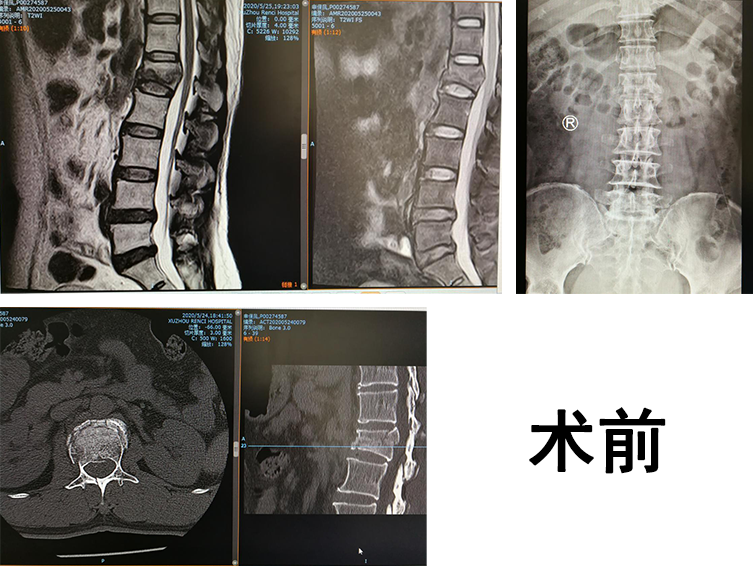

6月初,邳州市54岁的申大妈骑三轮车运货时,被迎面驶来的大货撞倒,申大妈臀部、右腕部着地,疼痛严重,不能活动,在当地镇卫生院行X线检查,显示腰1椎体爆裂性骨折,右桡骨远端骨折,申大妈听从医生建议,随后来到专业骨科医院betway在线登陆就诊。

sararz脊柱科孟磊副主任医师接诊,对申大妈进行了仔细的问诊与检查,患者腰1椎体爆裂性骨折,是临床上比较复杂且严重的创伤,必须尽早手术治疗。尚军科主任和脊柱手术小组讨论后,决定采用骨科机器人辅助手术。孟磊副主任医师、孙玉龙医师、张宇翔医师手术团队为患者进行了机器人辅助下腰1椎体骨折闭合复位内固定术+右桡骨骨折复位外固定支架+克氏针固定术。

手术中,先由C型臂对患者进行三维影像扫描,图像被同步传输至骨科机器人系统。手术医生在导航系统屏幕上设计好钉道,机器人的机械臂将手术工具精确定位到手术位置,套筒指向目的钉道的进钉点,从而实现螺钉的精准安全植入。随后,手术小组对右桡骨骨折进行处理,复位骨折端,克氏针固定,安装桡骨远端骨折外固定架,打入骨钉,确定内固定位置良好。手术很成功。